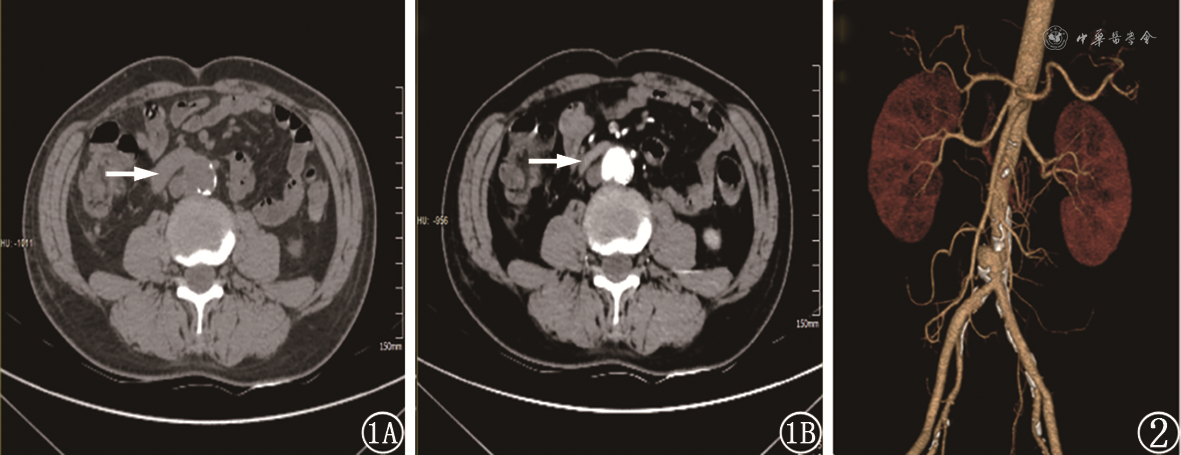

患者男,64岁,因“呕血、黑便4 d” 入院。患者无腹痛、发热。既往有冠心病病史,不规律服用阿司匹林。体格检查:血压105/53 mmHg,神志清楚,贫血貌,腹软,无压痛反跳痛。血常规:红细胞2.45× 109/L,Hb 67 g/L。胃镜和结肠镜检查提示胃、十二指肠球部降部和大肠均未见异常,腹部增强CT发现腹主动脉壁和双侧髂动脉壁多发钙化斑块,腹主动脉近髂总动脉分叉处呈瘤样扩张,约25 mm× 24 mm,瘤体凸向十二指肠水平部,和十二指肠之间的脂肪间隙消失,未见造影剂溢入毗邻肠腔(图1)。患者入院后第10天再次便血3次,总量约1 300 ml,并出现意识丧失,血压进行性下降,动脉血气Hb 37 g/L,乳酸6 mmol/L,转入普外ICU给予输血和抗休克治疗。患者循环稳定后急诊行血管造影未见造影剂外溢,剖腹探查术中行胃十二指肠镜检查见胃腔和十二指肠球部、降部大量新鲜血液和血凝块,无出血点,十二指肠水平部有活动性出血,遂切开十二指肠探查,可见十二指肠水平部有一小溃疡,溃疡中心喷射状出血,与腹主动脉瘤相通,压迫出血时可触及肠壁外搏动的腹主动脉和质硬的腹主动脉钙化斑块,结合术前增强CT术中诊断:主动脉十二指肠瘘(aortoduodenal fistula,ADF)。行腹主动脉十二指肠瘘缝合关闭+胃窦离断关闭+胃空肠毕Ⅱ式Roux-en-Y吻合。术后出血停止,术后第5天行CT主动脉造影血管三维重建提示腹主动脉瘤,未见造影剂外溢(图2)。术后第20天患者再次出现便血,急诊行腹主动脉覆膜支架植入后患者再无消化道出血,痊愈出院。